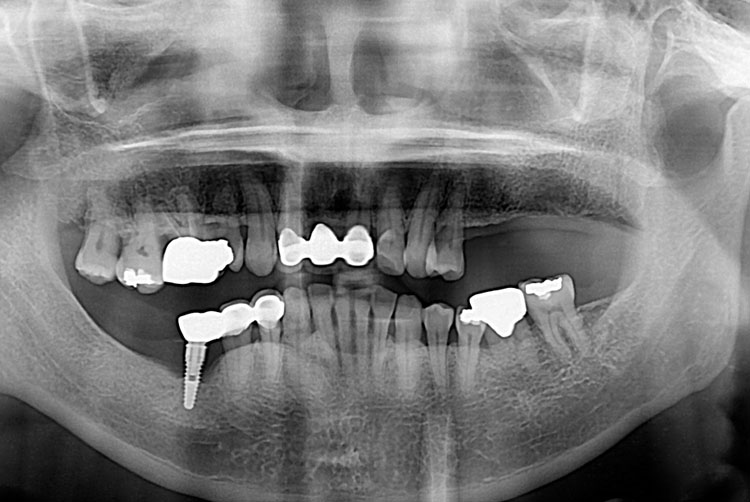

치료전 : 2019-06-13

유정림_후.jpg

치료후 : 2019-08-08

세종치과는 많은 환자와 다양한 케이스를 바탕으로 항상 편안한 임플란트 수술을 제공하고자 노력하고,

오래동안 튼튼히 쓸 수 있는 임플란트 수술을 가장 큰 목표로 삼고 있습니다.